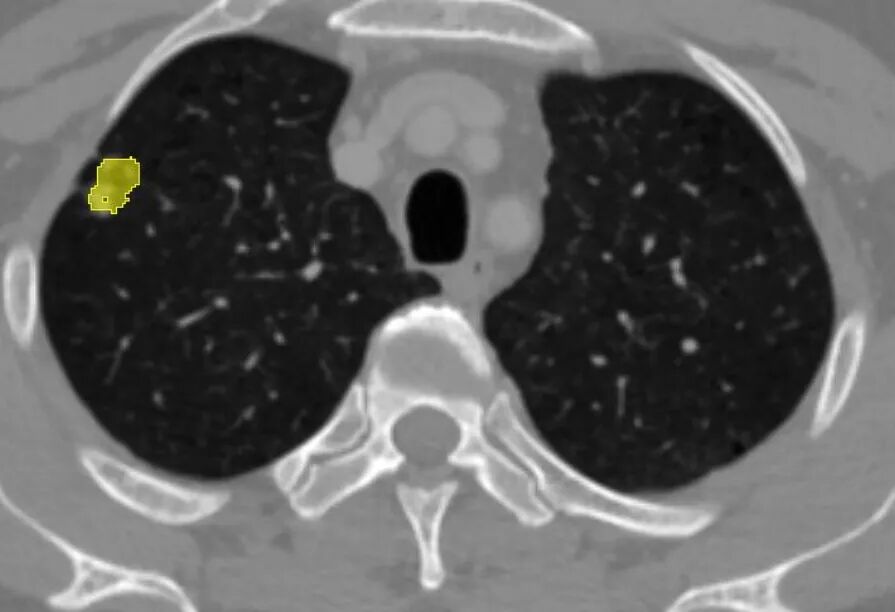

术前精准诊断:全面评估病灶影像学特征,直观展示解剖空间结构,帮助完善术前诊断与规划

术中精准定位:准确识别毗邻组织与病灶相对位置,精确测量显示解剖边界,辅助勾画手术切缘